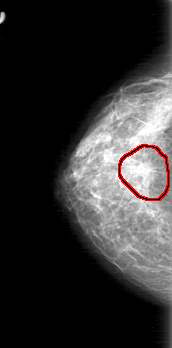

D_4030_1.RIGHT_CC

RIGHT_CC LINES 5206 PIXELS_PER_LINE 2566 BITS_PER_PIXEL 12 RESOLUTION 43.5 OVERLAY

FILE: D_4030_1.RIGHT_CC.OVERLAY

TOTAL_ABNORMALITIES 1

ABNORMALITY 1

LESION_TYPE MASS SHAPE IRREGULAR MARGINS SPICULATED

ASSESSMENT 5

SUBTLETY 5

PATHOLOGY BENIGN

TOTAL_OUTLINES 1

BOUNDARY